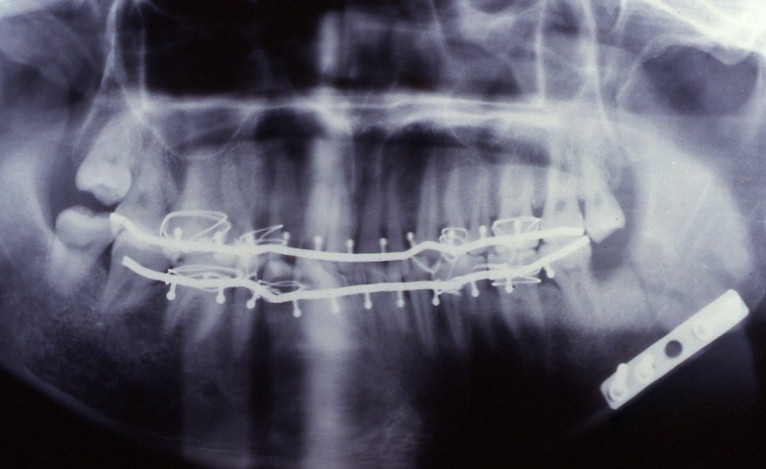

症例3

建設作業中に高所より転落して受傷。

写真は手術後のもので、三内式シーネによる顎間固定をして咬合を回復し、金属プレートで骨接合をしました。